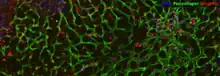

PCLS provide a robust ex vivo model; they maintain the liver's complex structure. PCLS are used for investigating mechanisms of liver injury and identifying therapeutic targets.[4][5][6]